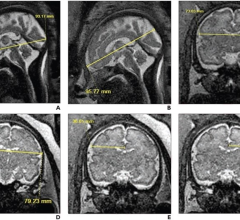

January 27, 2023 — According to an accepted manuscript published in ARRS’ American Journal of Roentgenology (AJR), both ...